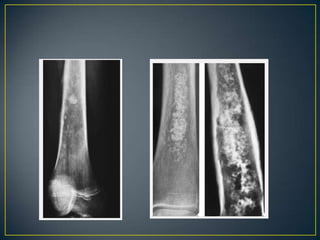

• Only two of these—osteoblastic and cartilaginous

tissue—can usually be clearly demonstrated

radiographically.

• Identification of tumor bone within or adjacent to the area

of destruction should alert the radiologist to the possibility

of osteosarcoma/reactive sclerosis.

• Osteosarcoma-cloudy - cotton like fluffy deposits.

• Cartilage is identified by the presence of typically

popcorn-like, punctate, annular, or comma-shaped

calcifications in lobules.

• A completely radiolucent lesion may be either fibrous or

cartilaginous .